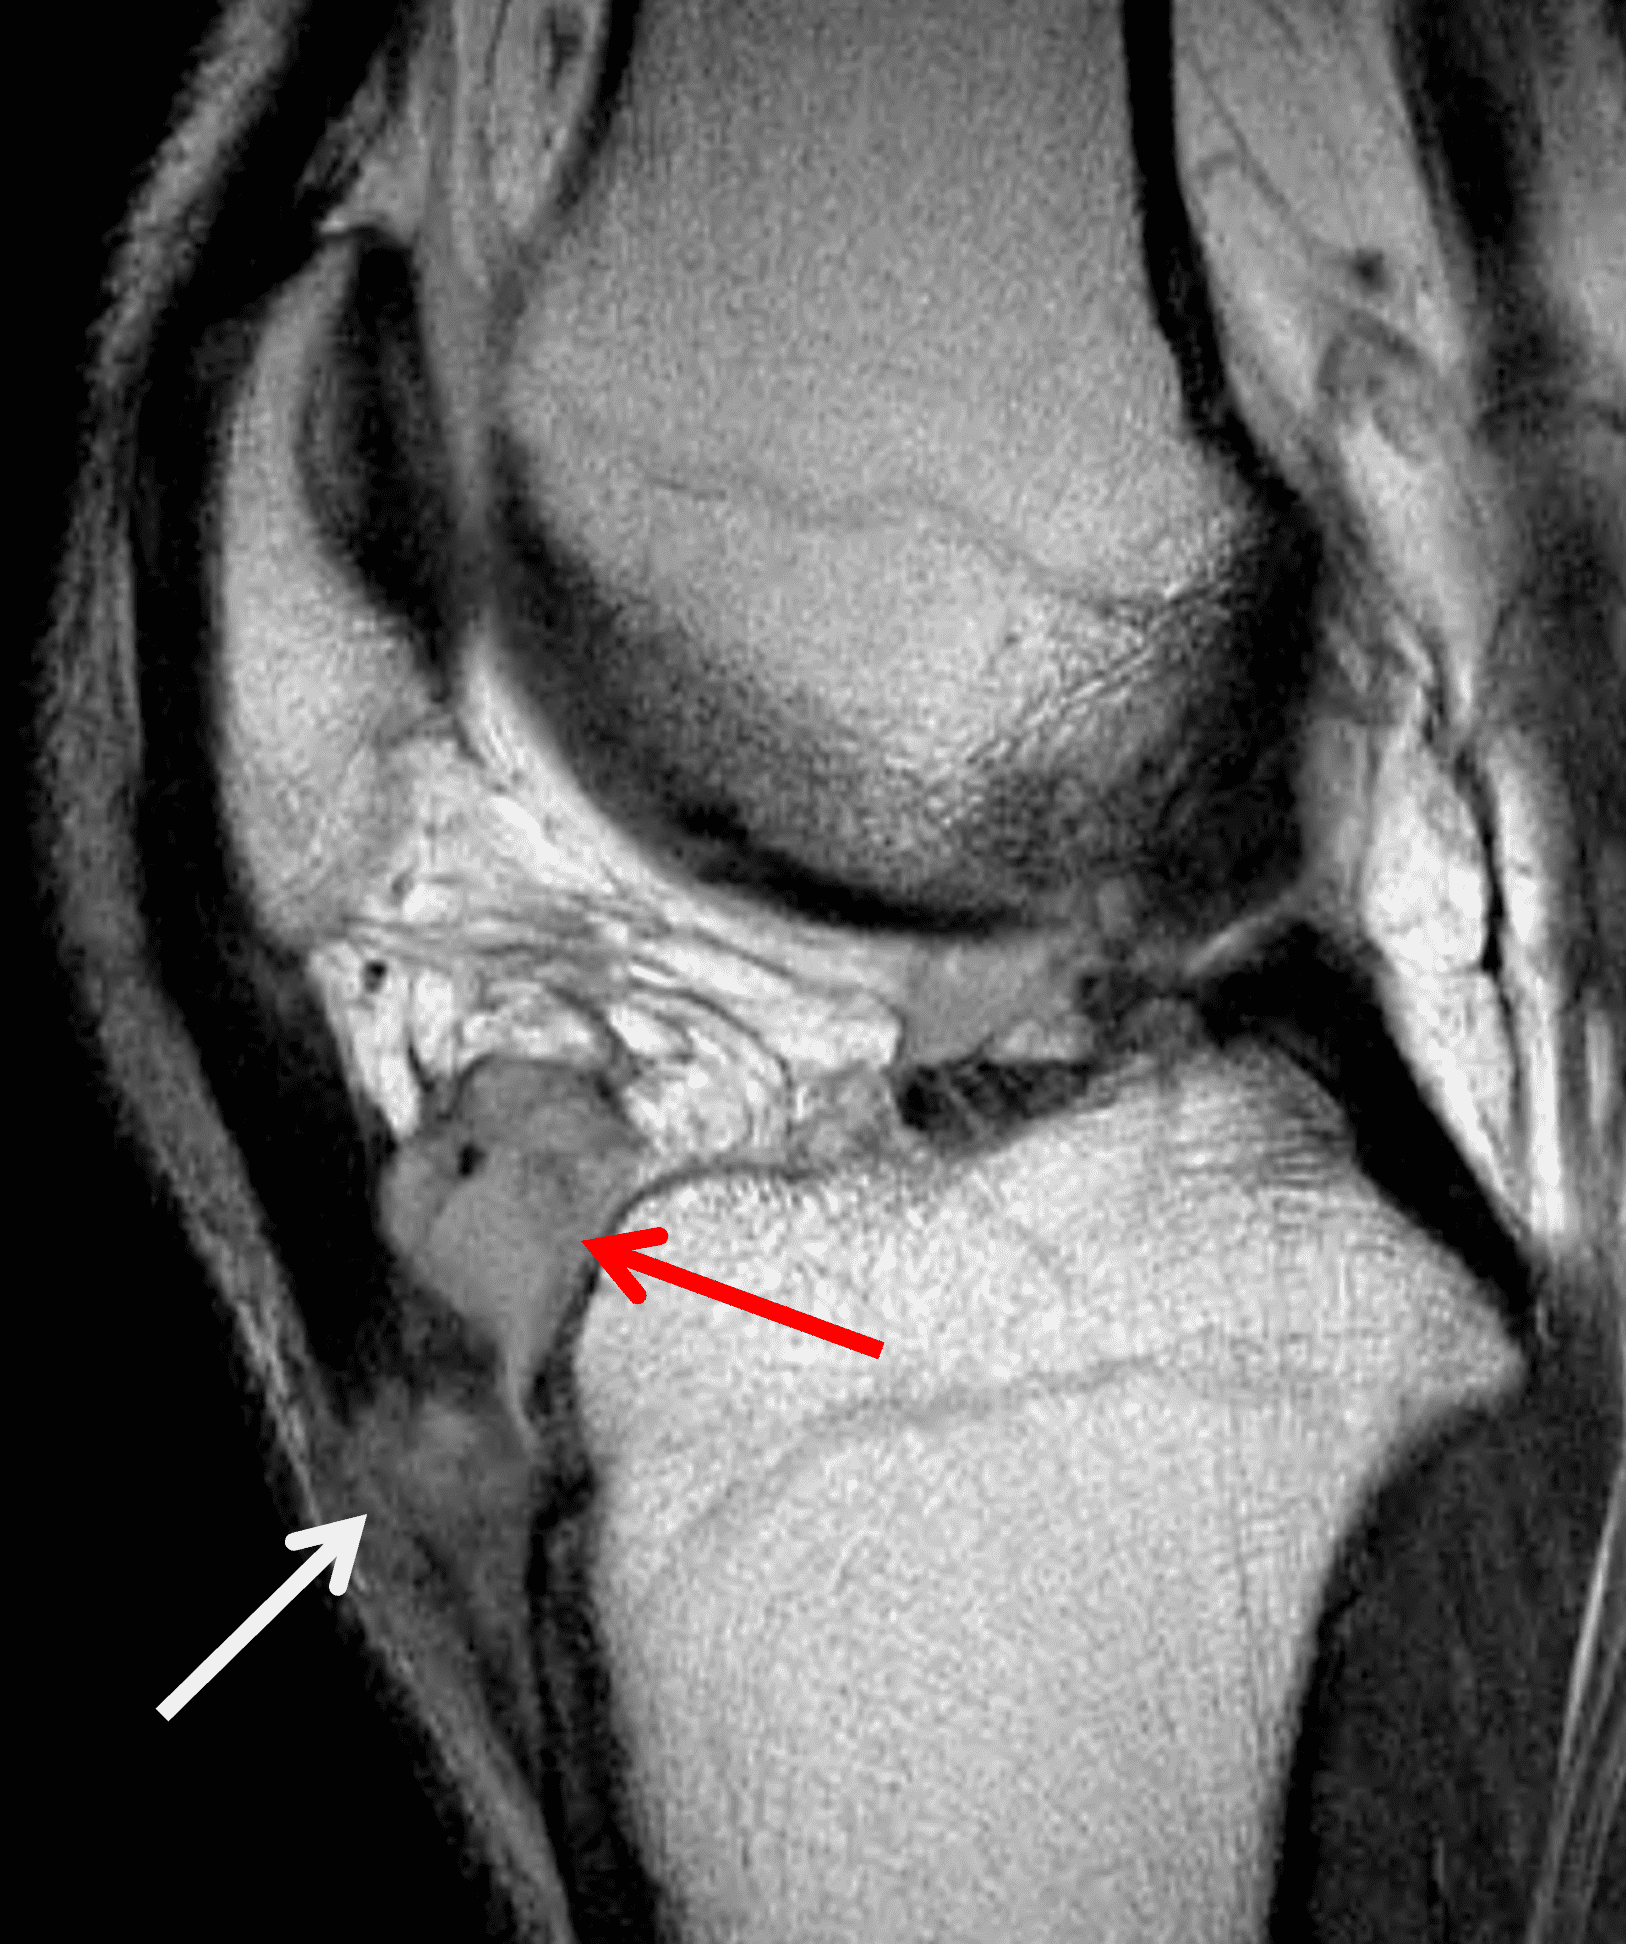

Figure 4: Lyme arthritis. Fat-suppressed, fluid-sensitive images. (4A) Transverse image shows severe proliferative synovitis in the anterior and posterior joint recesses (arrows). Note the lack of surrounding subcutaneous edema. (4B) In addition to synovitis, the sagittal image shows multiple reactive lymph nodes (red arrows) and popliteal myositis (white arrow). (4C) Coronal image also shows patchy non-joint centered marrow edema in the distal femur and proximal tibia (asterisks), which is uncommon in Lyme disease compared to acute septic arthritis.

Pediatric patients often present with a more acute clinical picture including fever, difficulty weight-bearing, elevated serum inflammatory markers, and elevated synovial white blood cell count, all of which can also be seen in the setting of acute septic arthritis due to other bacteria.5,9,12 Several studies have identified MR findings that help distinguish Lyme arthritis from septic arthritis for clinical decision-making. Both groups of patients will have synovitis and an effusion related to synovial inflammation and hyperemia. However, subcutaneous edema is highly associated with septic arthritis (Figure 5) and uncommon in Lyme arthritis. Marrow edema and erosions are much more common in septic arthritis, while osteomyelitis – actual infection of the bone – only occurs septic arthritis.2,3,9 Myositis can be seen in both conditions, but severe diffuse myositis is more highly correlated with septic arthritis (Figure 5).2